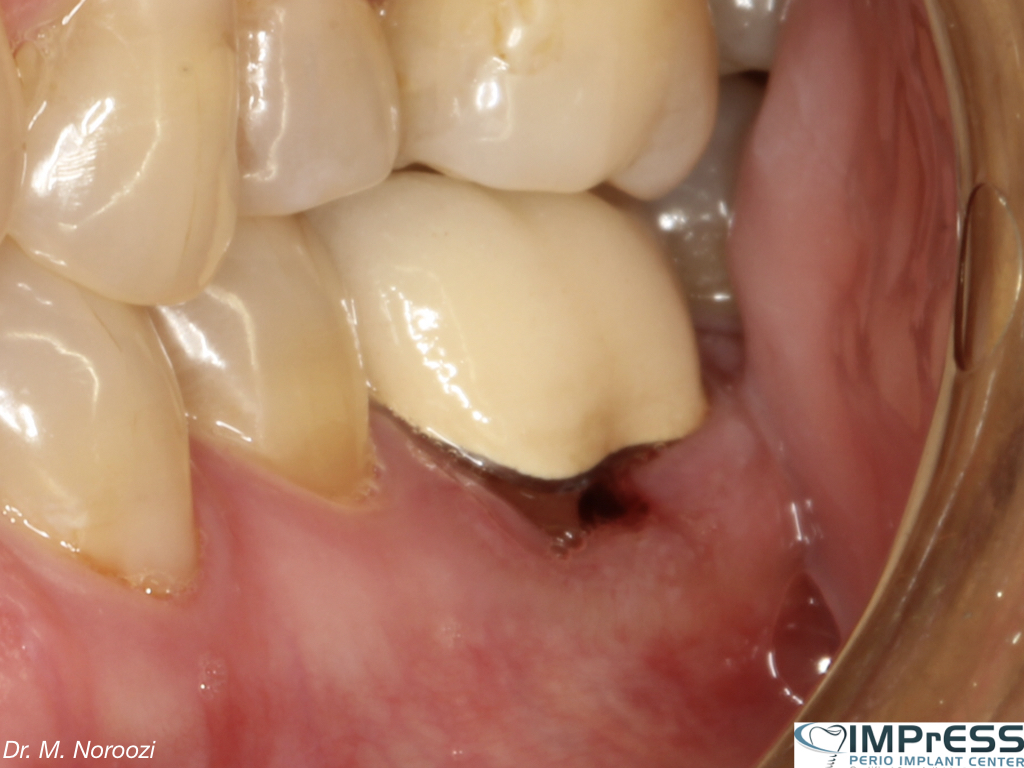

Failing Dental Bridge Being Replaced by Dental Implants